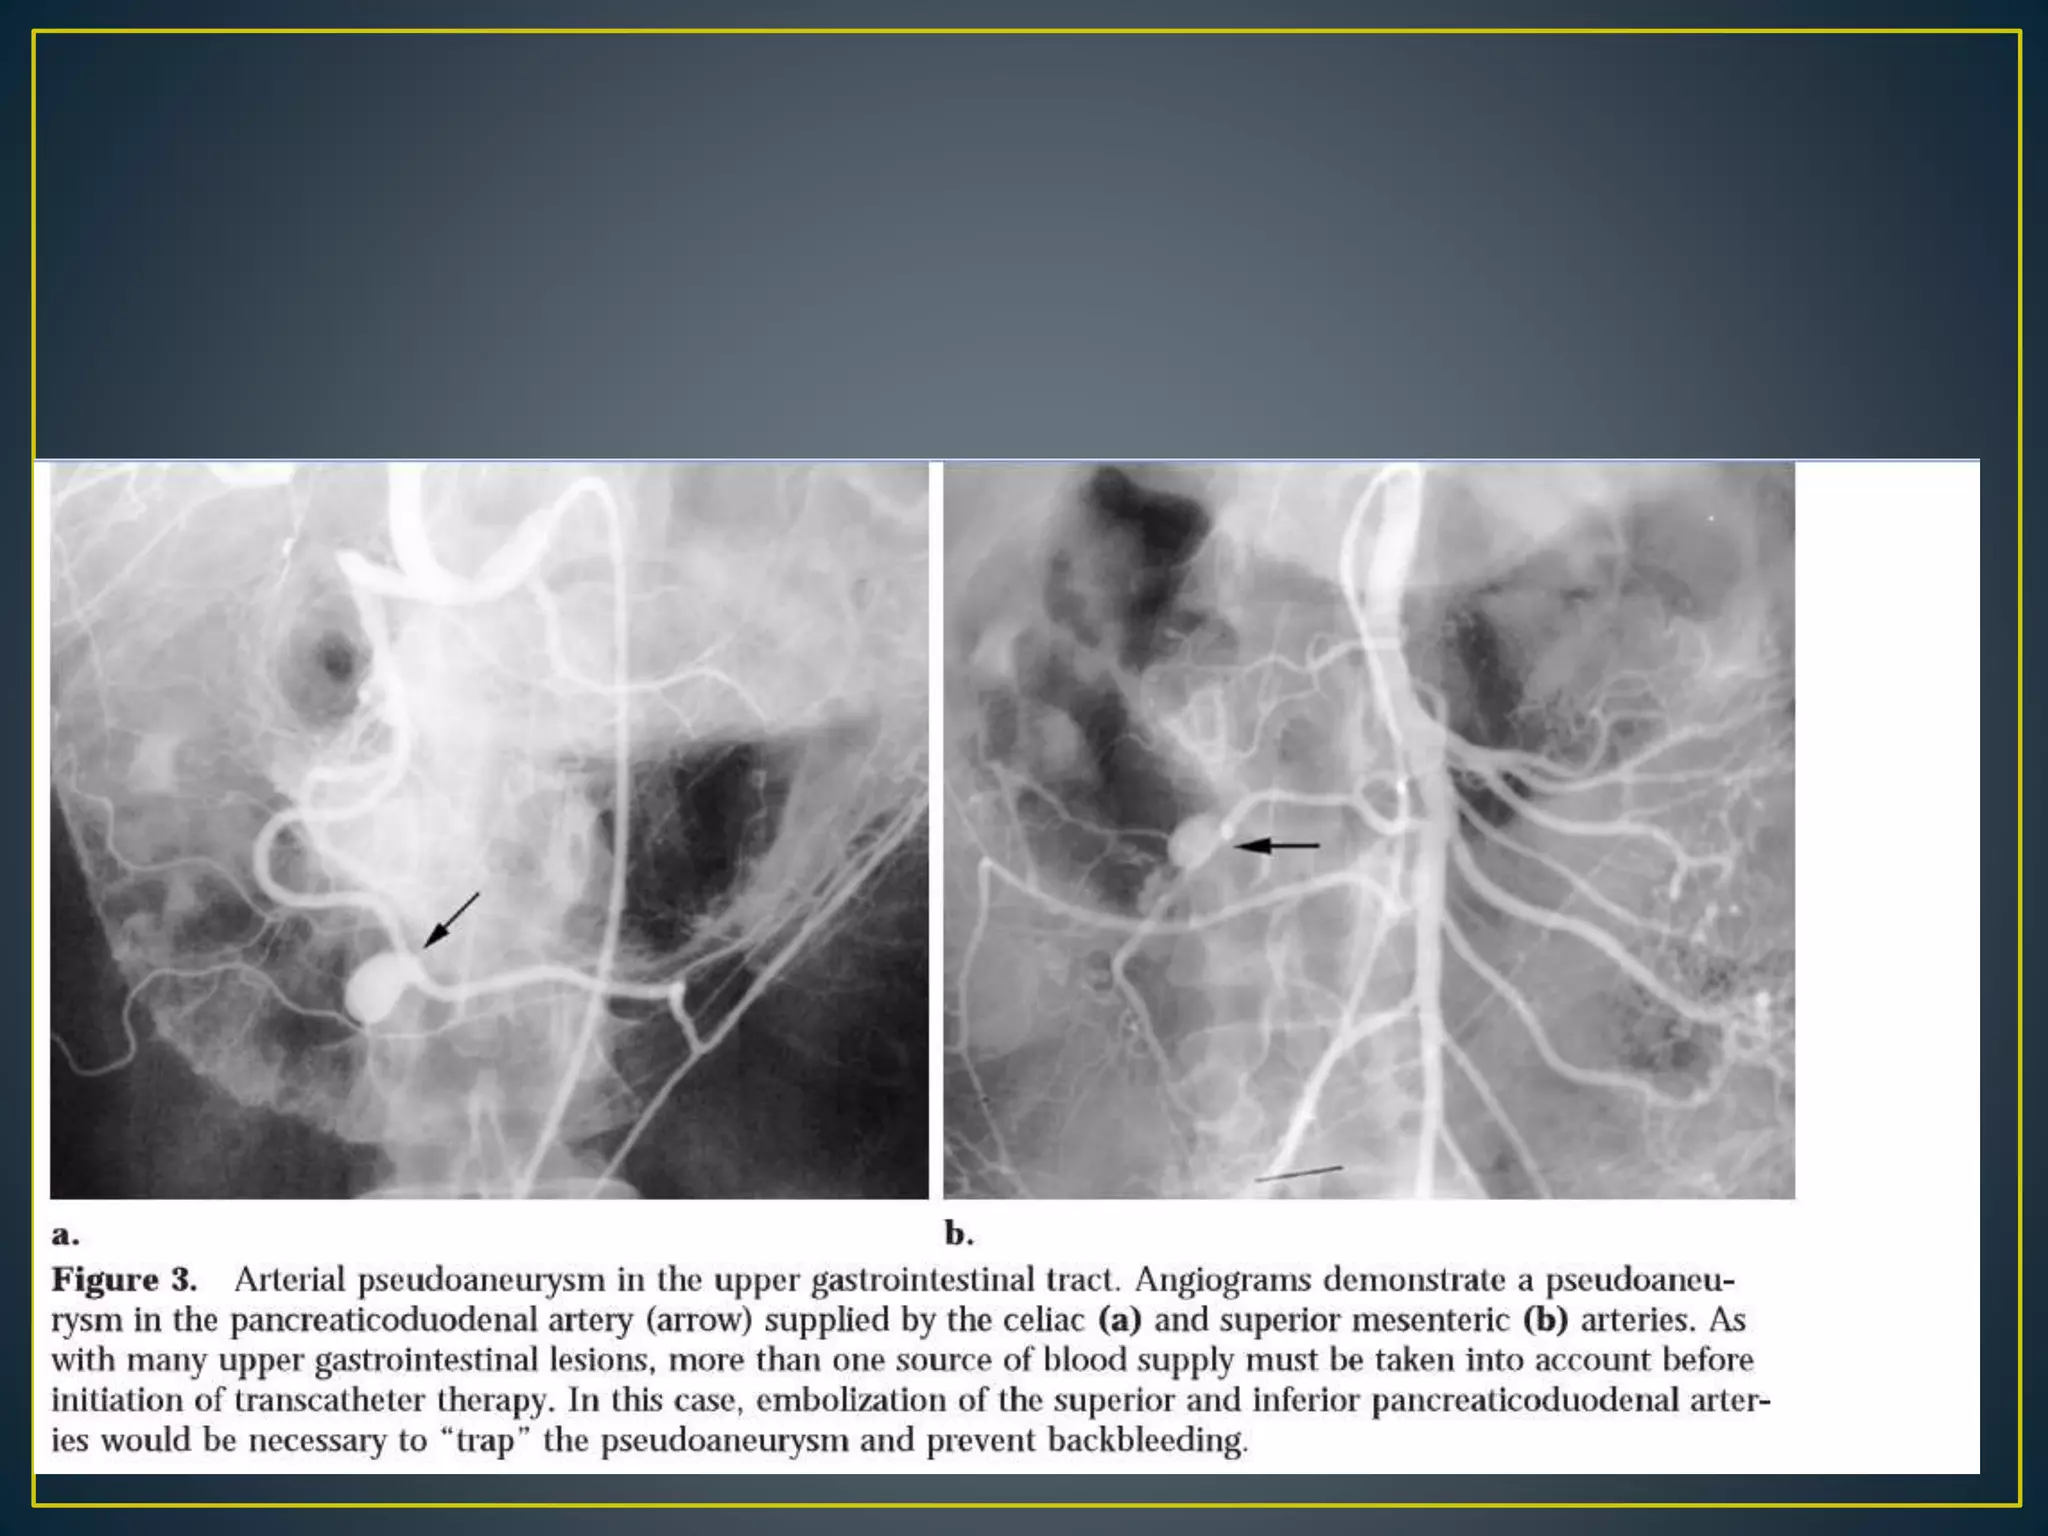

• pseudo aneurysm, also known as a false aneurysm, is

a hematoma that forms as the result of a leaking hole in

an artery. Note that the hematoma forms outside the

arterial wall, so it is contained by the surrounding tissues.

Also it must continue to communicate with the artery to

be considered a pseudo aneurysm.

• This must be distinguished from a true aneurysm which is

a localised dilatation of an artery including all the layers

of the wall.